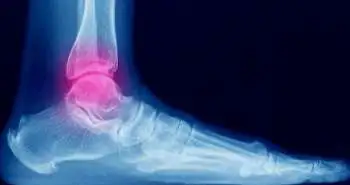

Fewer opioids may provide optimal pain relief in patients with ankle fractures as greater use of opioids did not improve pain, disability or treatment satisfaction after surgical management of ankle fractures.

The study elaborates onwhether opioid intake is concerned with disability, satisfaction with treatment, and pain at the time of suture removal and at 5 to 8 months after suture removal after open reduction and internal fixation of ankle fractures.